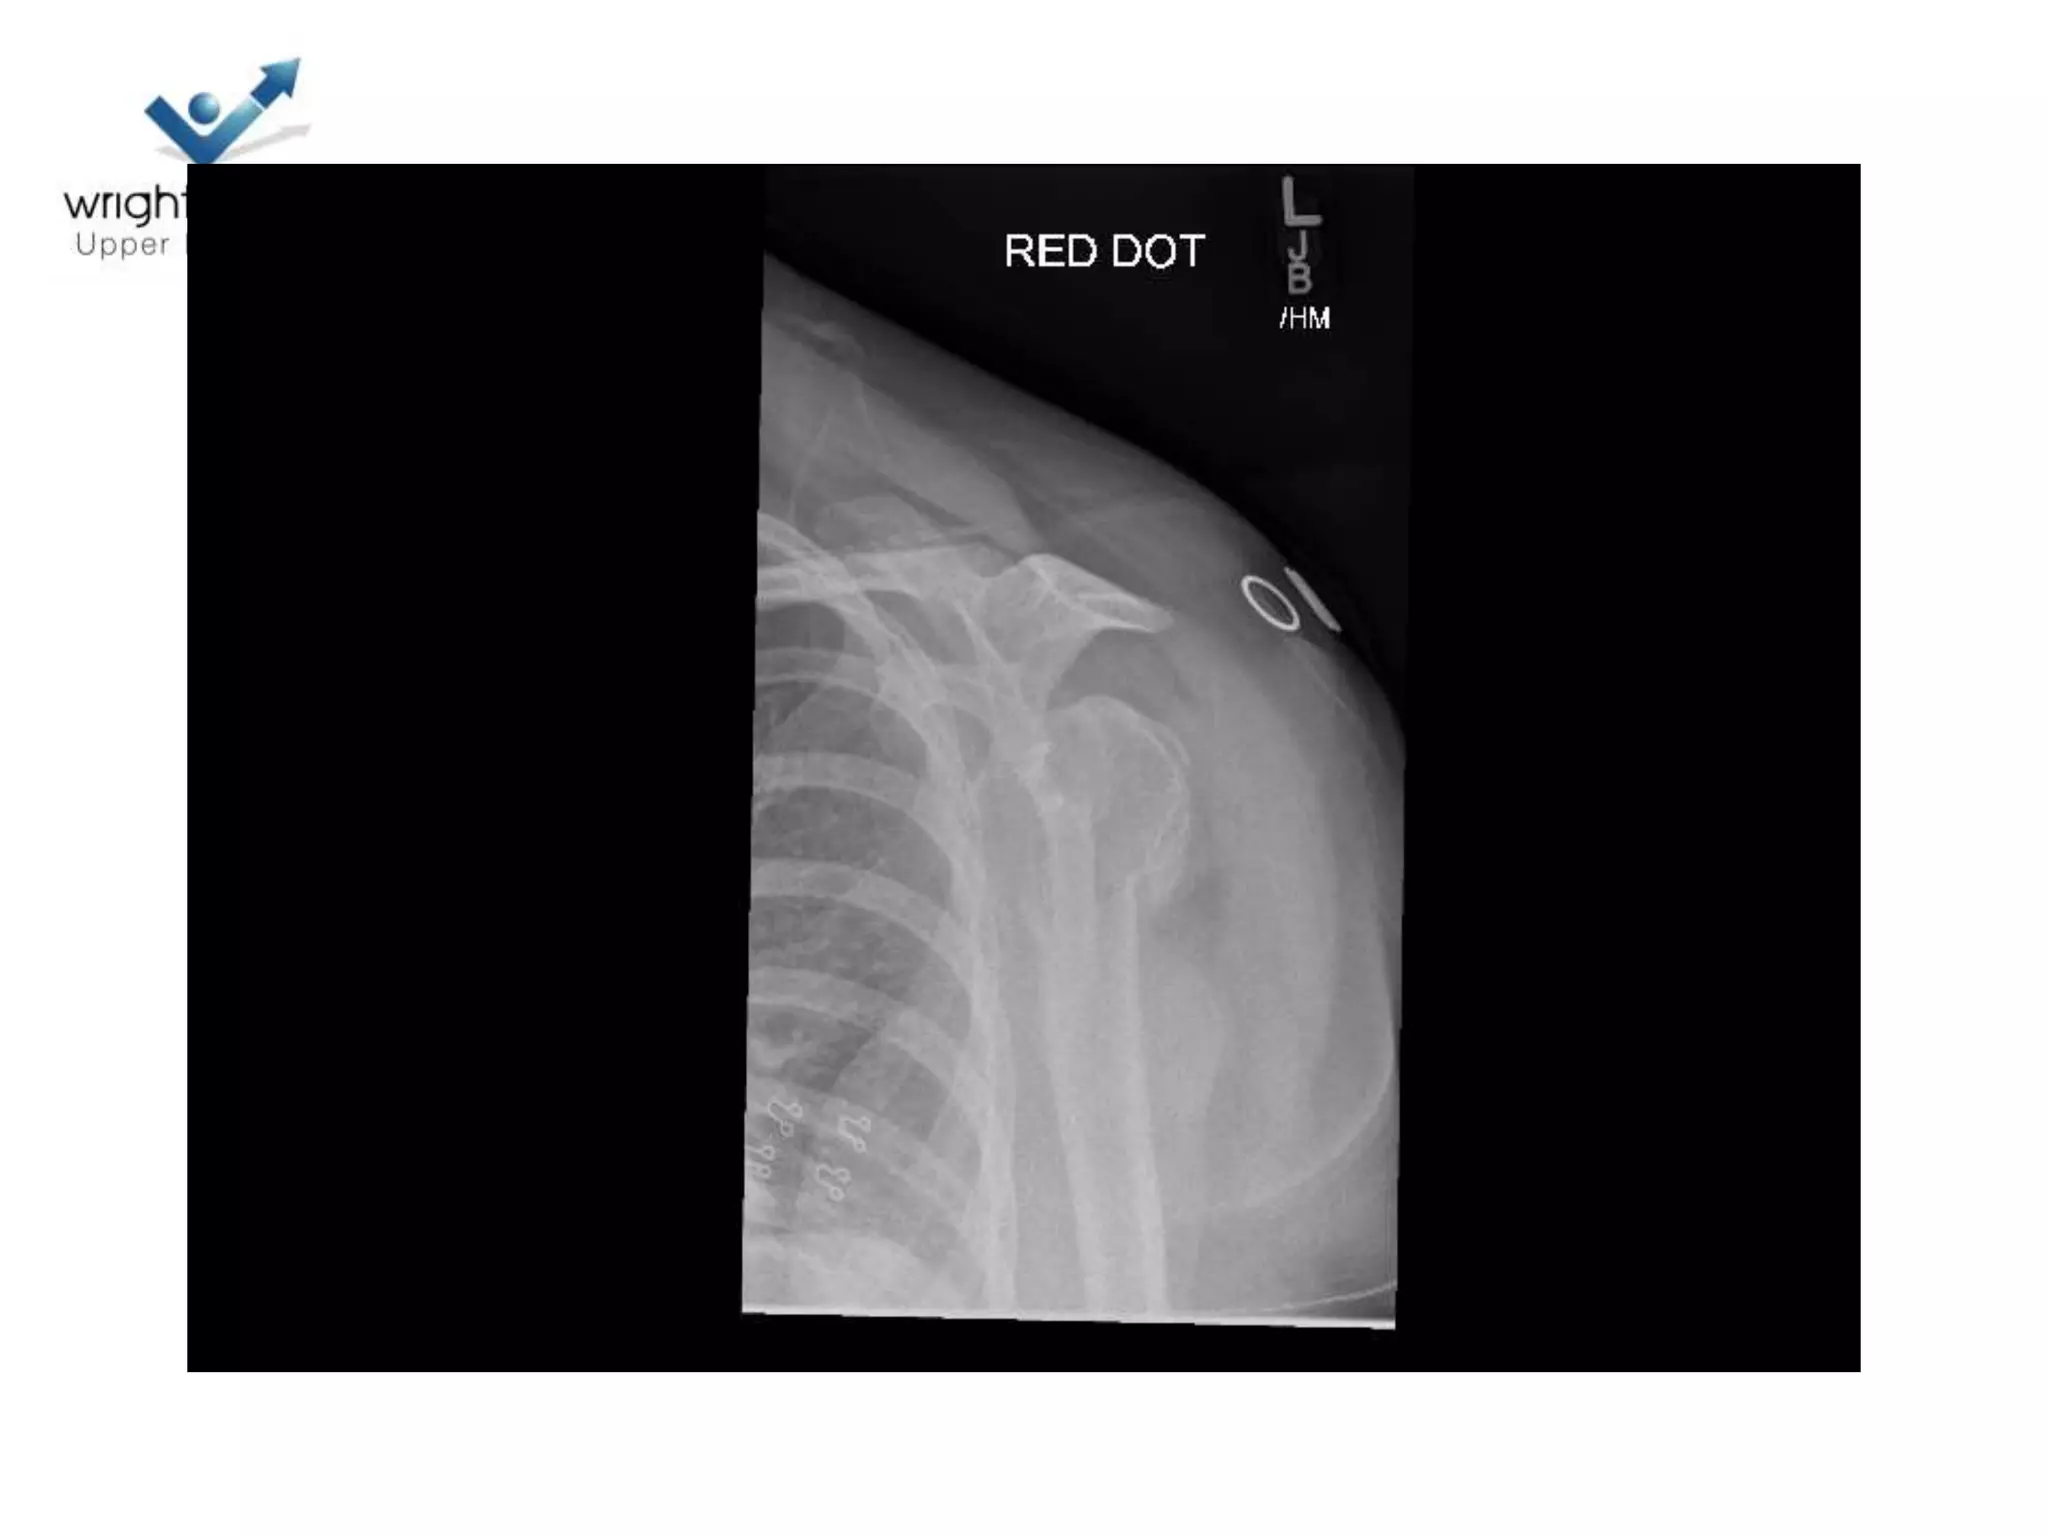

Case discussions

2 Next